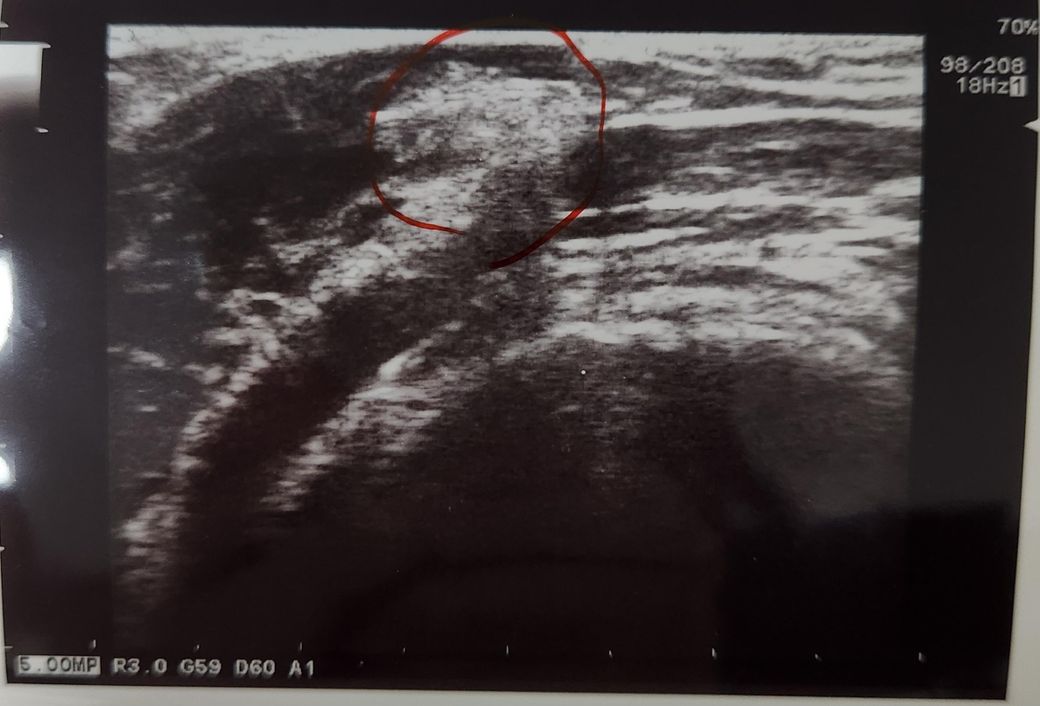

겨드랑이 초음파 결과 봐주세요ㅠㅠㅜ

왼쪽 겨드랑이에 통증없는 멍울이 2달동안 잡혀서 피부과에서 초음파 봤습니다 통증이 있으면 염증같다고 할텐데 제가 통증은 거의 없다고 하니까 뭔지 잘 모르겠다고 하셨어요 혹시 원인이 뭘지 짐작가시는 분 있으실까요??

• 1번 째 사진

겨드랑이에 멍울이 생기고 위의 사진으로 여러결과를 유추해볼 수는 있습니다

림프절 비대: 겨드랑이에는 림프절이 있습니다 감염이나 염증이 없더라도 림프절이 비대해질 수 있고 일반적으로 큰 문제가 아닐 수 있지만 지속되면 추가 검사가 필요할 수 있습니다

지방종: 피부 아래에 있는 양성 종양으로 통증이 없고 부드러운 덩어리로 느껴질 수 있습니다 일반적으로 수술적 제거가 필요하지는 않습니다

피부 낭종: 피부 아래에 생기는 낭종으로 종종 통증이 없고 멍울처럼 느껴질 수 있습니다

피부 병변: 드물게는 피부의 다른 병변이 원인일 수 있습니다

위와같은 상태를 추측해볼 수 있습니다

일단 멍울이 지속되거나 변화가 생기면 MRI나 CT 촬영을 해보시는것을 권해드립니다

요약하자면 통증이 없는 멍울은 여러원인에 의해서 발생할 수 있으며 보통은 큰문제가 아닙니다 하지만 멍울의 변화가 있거나 지속되면 꼭 대형병원에 가보시는것을 권해드립니다 제가 생각하기에는 지방종일 확률이 높아보입니다

지방종의 가능성도 있어보입니다.

추가 검사를 시행해서 확인 해보시기 바랍니다.